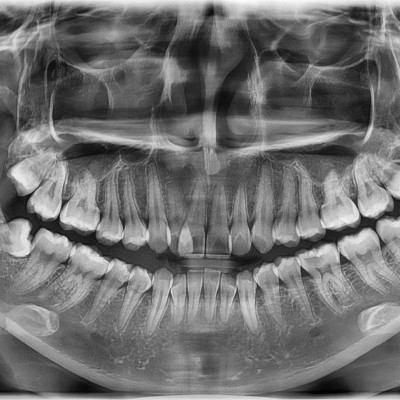

#18,28,38 48 사랑니 발치 #18,28,38,48 사랑니 발치 구강 외과 전문의가 당일 발치했습니다. ----------------------..

작성자 이턱이 작성일 02-04 조회 1